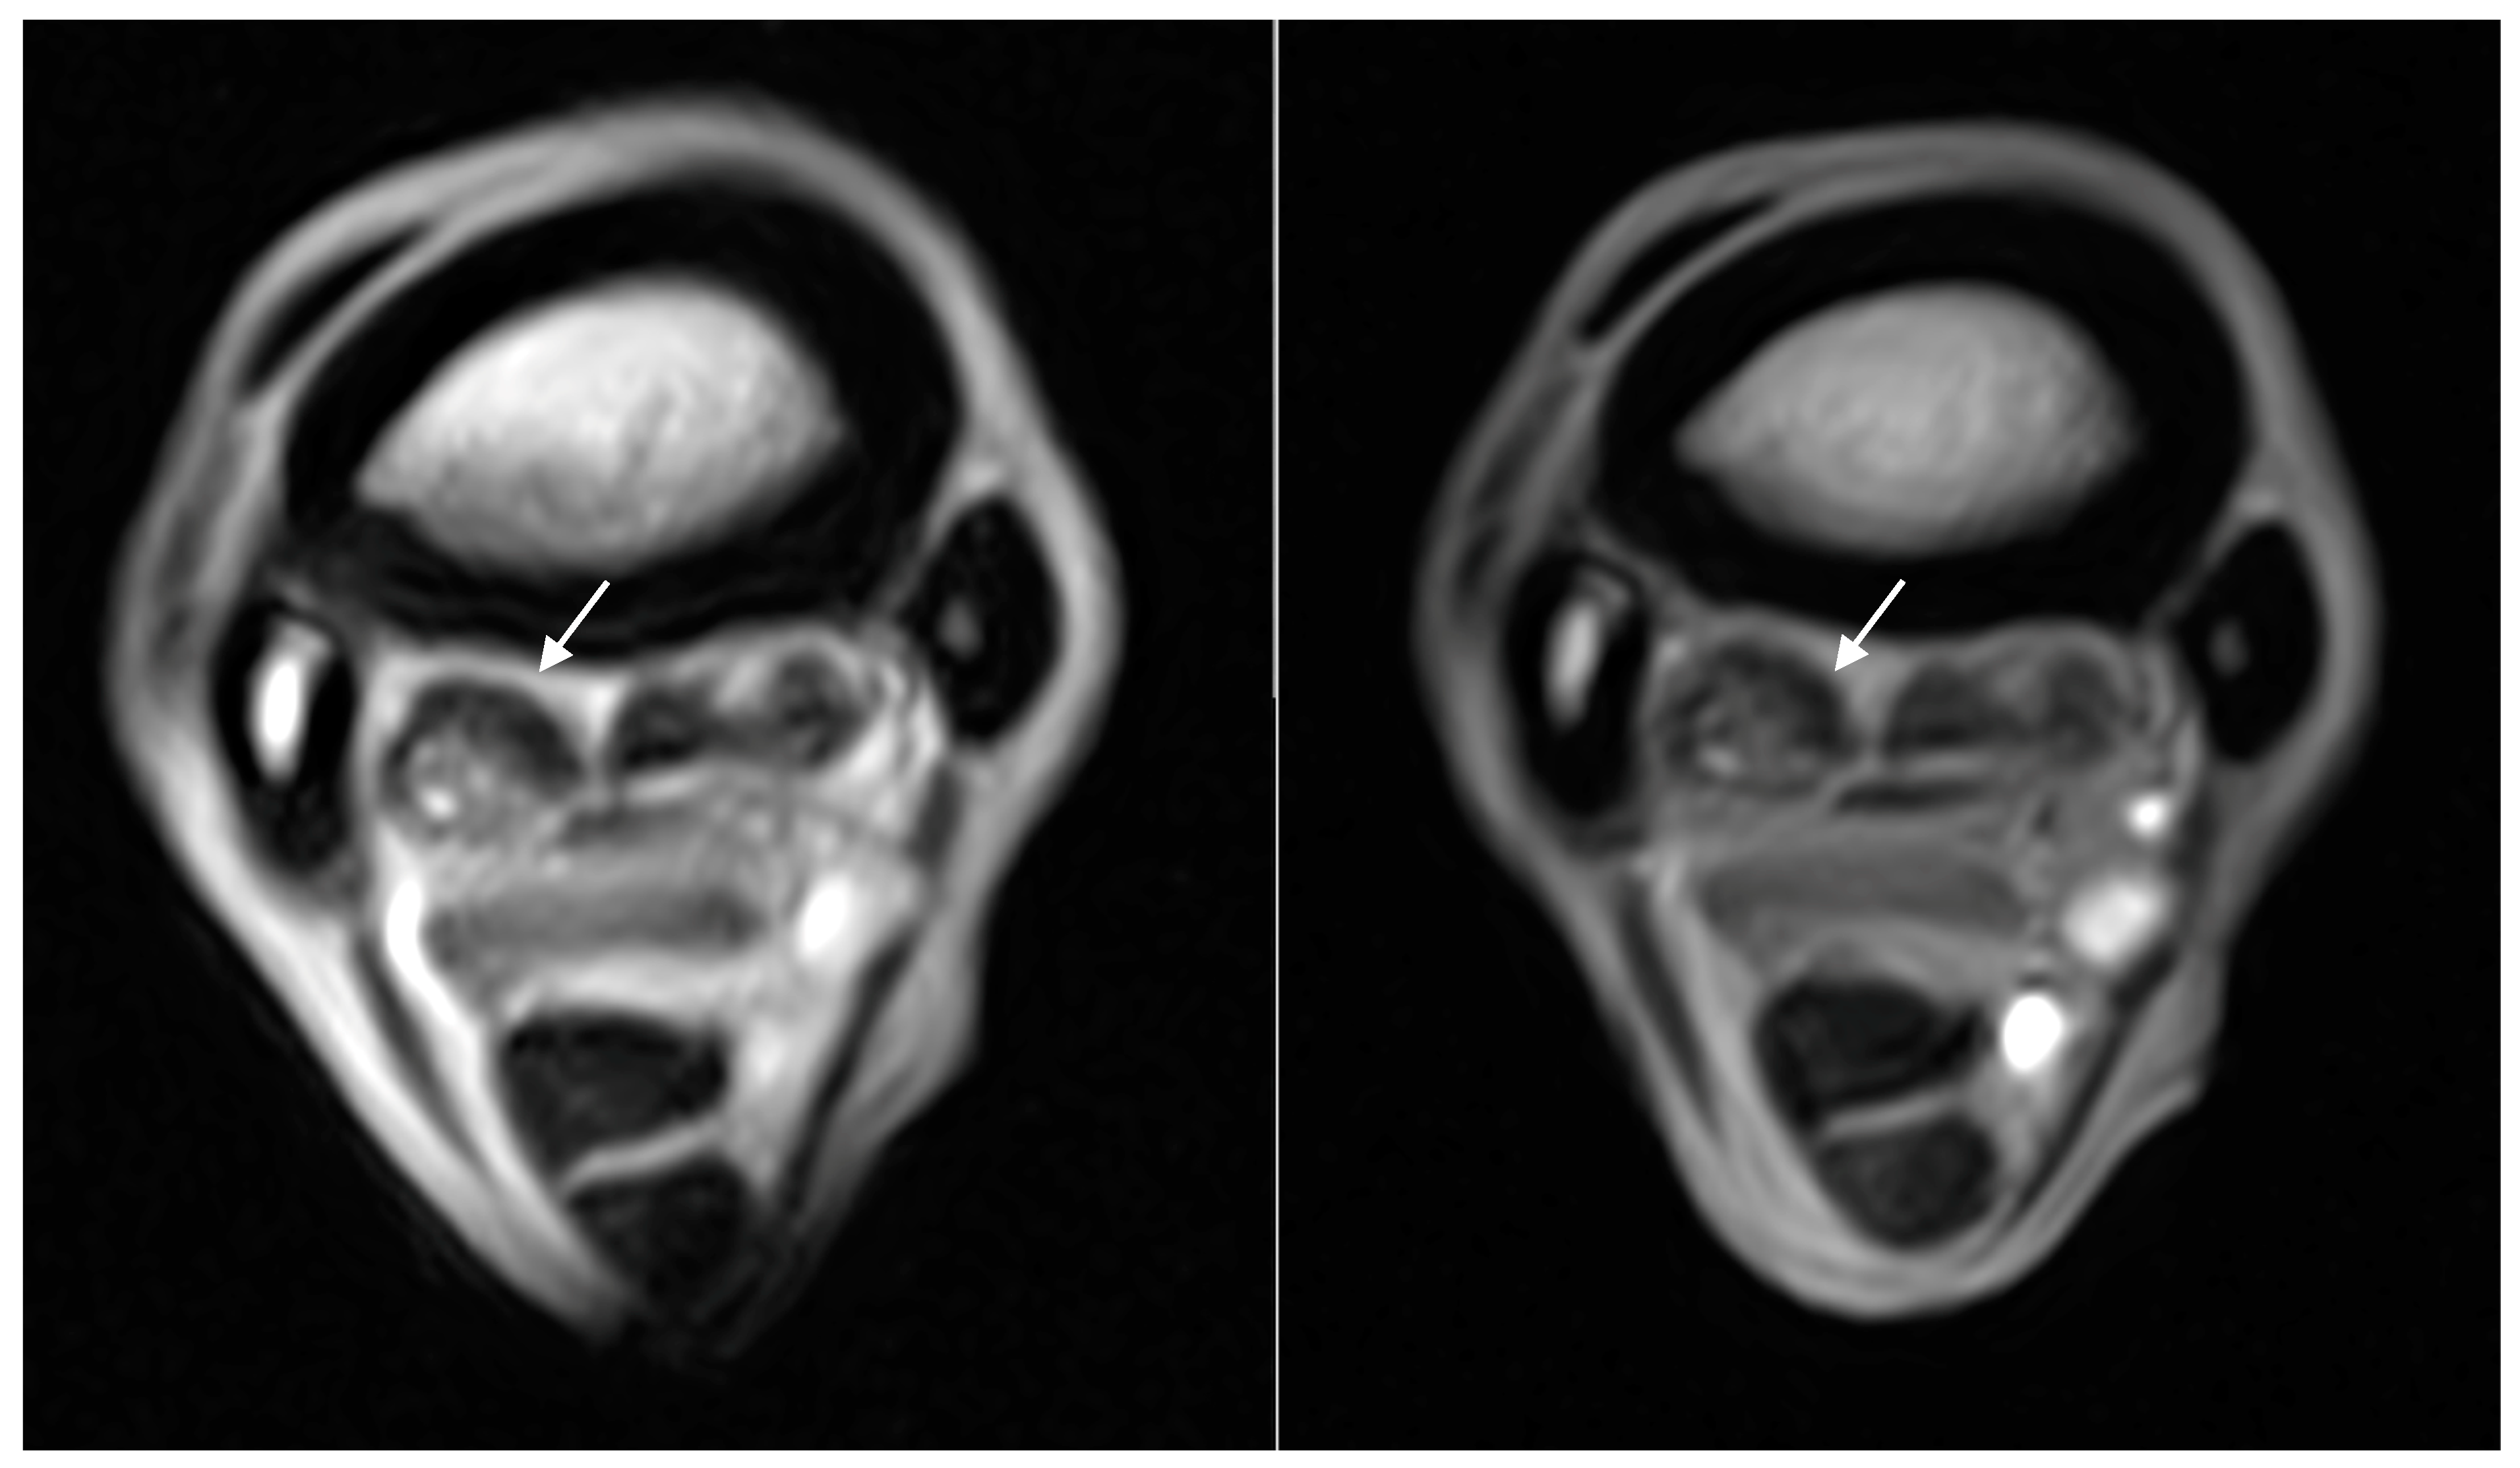

| Hyperintense signal on T1W GRE and T2*W GRE within the dorsal collagenous part of the PSL | 11/18 (61%) | 0/11 | 6/11 (55%) | 4/11 (36%) | 1/11 (9%) |

| Hyperintense STIR signal within the dorsal collagenous part of the PSL | 5/18 (28%) | 4/5 (80%) | - | 1/5 (20%) | - |

| Hyperintense signal on T1W GRE and T2*W GRE within the dorsal collagenous part of the PSL | Grade 0: 7 limbs Grade 1: 5 limbs Grade 2: 5 limbs Grade 3: 1 limb | Grade 0: 7 limbs Grade 1: 10 limbs Grade 2: 1 limbs Grade 3: 0 limbs |

| Hyperintense STIR signal within the dorsal collagenous part of the PSL | Grade 0: 13 limbs Grade 1: 1 limb Grade 2: 4 limbs Grade 3: 0 limb | Grade 0: 17 limbs Grade 1: 0 limbs Grade 2: 1 limbs Grade 3: 0 limbs |